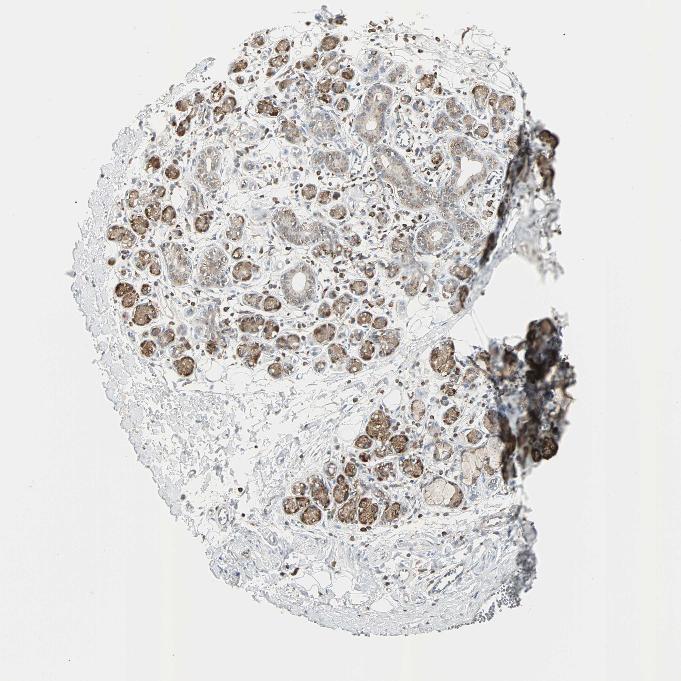

SOFT TISSUE 1 - Antibody stainingi

Antibody staining in the annotated cell types in the current human tissue is reported as not detected, low, medium, or high, based on conventional immunohistochemistry profiling in selected tissues. This score is based on the combination of the staining intensity and fraction of stained cells.

Each image is clickable and will lead to virtual microscopy that enables deeper exploration of all samples and also displays staining intensity scores, fraction scores and subcellular localization as well as patient and tissue information for each sample.

Antibody HPA006979

Chondrocytes Not detected

Fibroblasts Not detected

Peripheral nerve Not detected